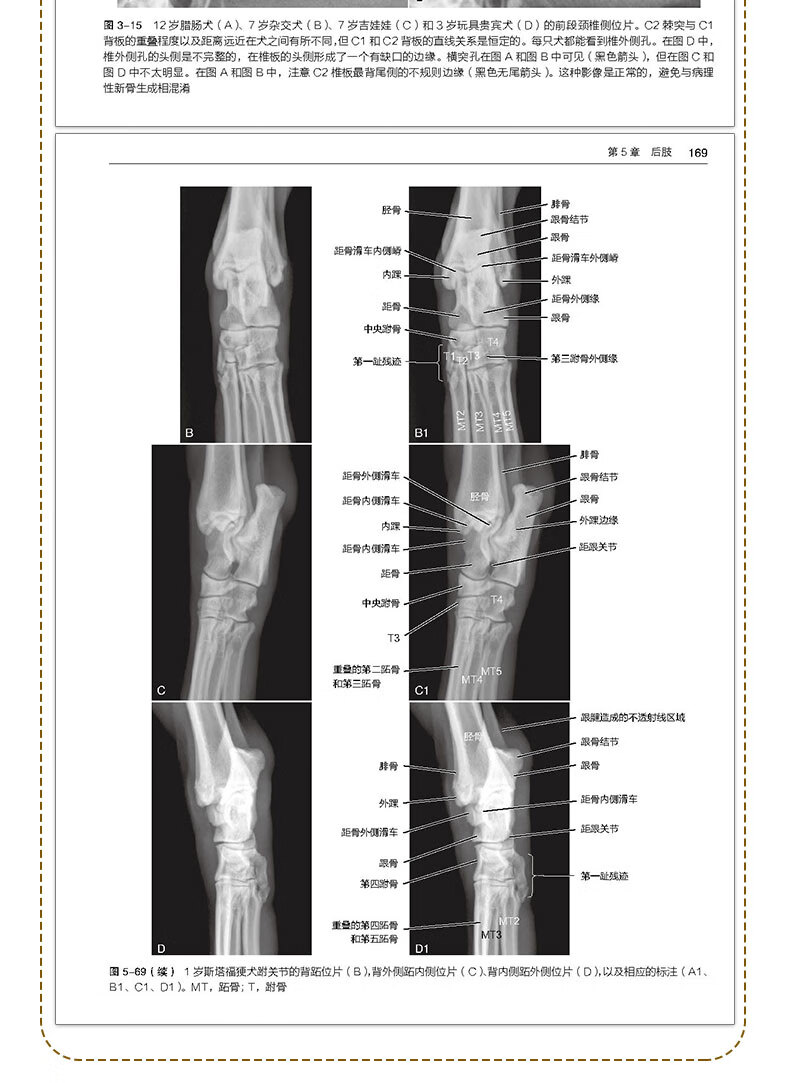

【犬猫正常放射影像解剖與變化圖譜】